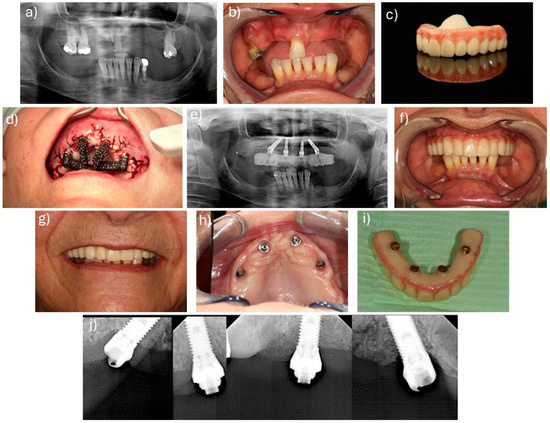

Facially Driven Full-Arch Implant Rehabilitation with Stackable Metallic and Magnetic Surgical Guides and Immediate Loading: Our Clinical Experience and Scoping Review

by Ioan Sîrbu, Vladimir Nastasie, Andreea Custura, Adelin Radu, Alexandra Tuţă, Valentin Daniel Sîrbu, Bogdan Andrei Bumbu, Tareq Hajaj, Robert Avramut, Gianina Tapalaga and Serban Talpos

Dent. J. 2025, 13(11), 516; https://doi.org/10.3390/dj13110516 - 5 Nov 2025

Background: Stackable metallic or magnetic multi-template systems translate a prosthetically (facially) driven plan into each surgical phase of full-arch rehabilitation. Our objective was to map and critically describe the clinical applications, accuracy, and short-term outcomes of stackable/sequential guides and to illustrate the [...] Read more.

Background: Stackable metallic or magnetic multi-template systems translate a prosthetically (facially) driven plan into each surgical phase of full-arch rehabilitation. Our objective was to map and critically describe the clinical applications, accuracy, and short-term outcomes of stackable/sequential guides and to illustrate the operational steps with a standardized magnet-retained case. Methods: Following a prospectively registered protocol (OSF, June 2025), we performed a scoping review in accordance with and PRISMA guidance. PubMed, Scopus and Embase were searched to 26 June 2025 for primary human studies using stackable or sequential static guides to place ≥4 implants per arch with immediate (≤72 h) loading. Duplicate-independent screening and data-charting captured guide design, planning platform, surgical accuracy, implant survival, prosthetic outcomes and patient-reported measures. A single non-analytic clinical vignette was included solely to illustrate the facially driven stackable workflow. Results: Eight studies (five countries, 2021–2025) encompassing 351 implants and one additional clinical case met the inclusion criteria. Mechanical indexing predominated (7/9 protocols); only two papers, including our case, used magnetic retention. Mean coronal and angular deviations, reported in two cohorts, were 0.95 mm/2.8° and 0.87 mm/2.67°, respectively—well within accepted thresholds for full-arch guided surgery. Immediate loading was achieved in 100% of arches; cumulative implant survival was 97.1% after 3–12 months. Patient-reported satisfaction exceeded 90 mm on VAS scales when measured. Our case demonstrated 0.90 mm/2.95° accuracy, 100% implant stability ≥ 35 N cm and uneventful provisionalisation at 12 weeks. Conclusions: Early clinical reports show clinically acceptable accuracy and high short-term survival with streamlined workflow. However, evidence remains heterogeneous and short-term; prospective multi-centre studies with standardized accuracy metrics, ≥3-year follow-up, validated PROMs, and cost-effectiveness analyses are still needed. Full article